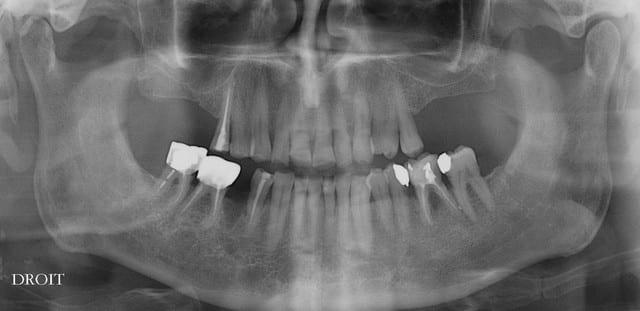

Nouveau patient, pose d'un implant il y a 2 mois....échec sans raisons particulières, douleurs et dépose.

Ce matin repose d'un nouvel implant et comme je ne veux pas prendre de risque, et que les dents adjacentes doivent être couronnées, je pose un bridge en emax press, mais scellé au ciment provisoire...

alors là pas du tout, le patient vient me voir pour des implants, donc je fais une étude du cas absence des molaires supérieures, couronnes mandibulaires très ancienne 45 racine cassée, 44 dévitalisée mais passablement déchaussée, donc avulsion de 45 et pose d'un implant avant de refaire les couronnes 46/47 et l'ensemble.

Échec implantaire, et oui ça arrive, même dans un cas paraissant simple.

Pour les septiques, toujours certain que c'est du sur-traitement?

pourquoi ne pas remplacer la 7 avant tout ?

et la l'implant s'impose ...